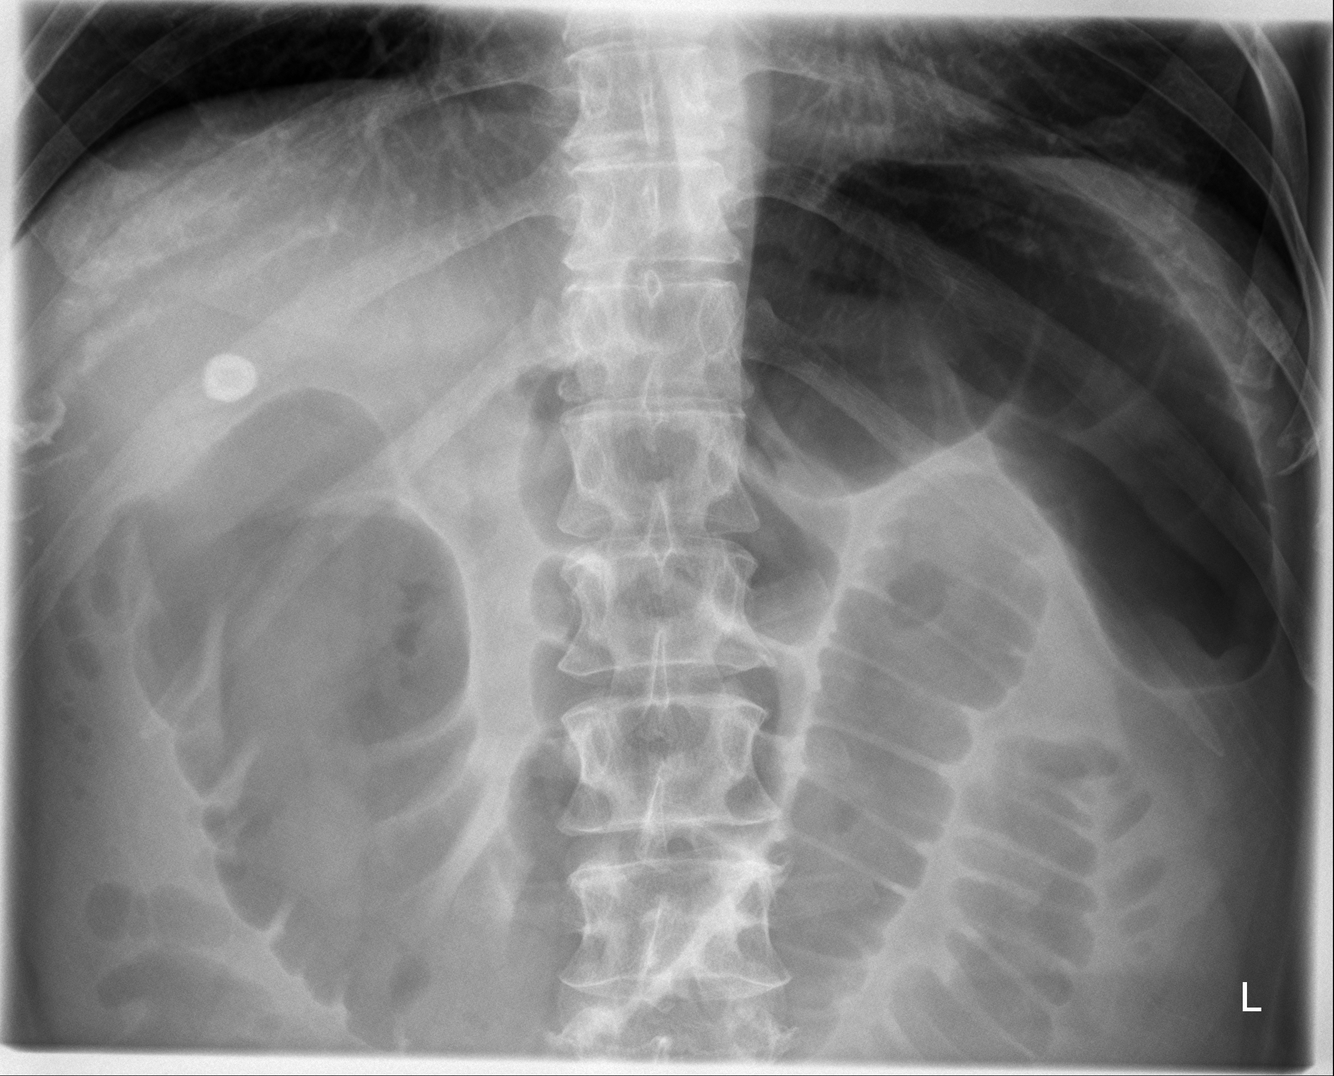

Thick punctate pancreatic calcifications with dilatation of duct of Wirsung. Distended gallbladder. Decreased liver attenuation coefficient, probably due to fat infiltration.

No focal hepatic lesions are observed. Normal adrenal glands and kidneys. No ascites or retroperitoneal lymphadenopathy are observed.

Case Discussion

This case shows typical findings of chronic pancreatitis with calcification and main duct dilatation. This is most commonly associated with chronic alcohol abuse as was the case for this patient.